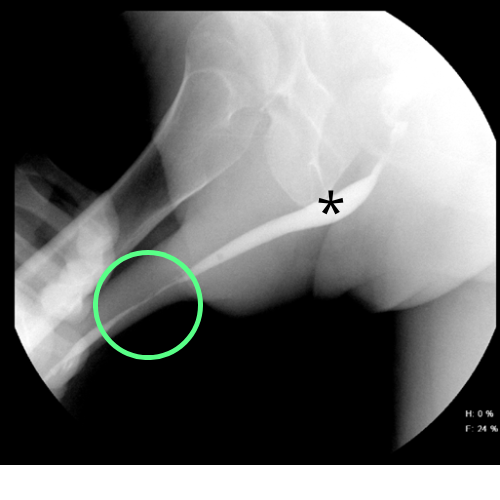

Imagen de estudio urodinamico - Jordán Scherñuk

Imagen que ilustra el registro de las presiones de la vía urinaria durante un estudio urodinámico computarizado